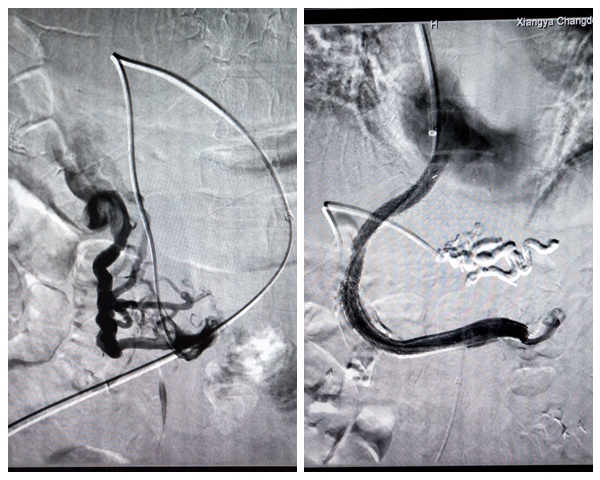

在中南大学湘雅医院外周介入专家李海平教授带领下,汤金城医师、李毅副主任医师和黄彬副主任医师共同为患者实施了经静脉肝内门-体分流术(TIPS)+门静脉-脾静脉支架植入术+食管胃底静脉栓塞术。手术历时3个小时,术中患者无明显不适,术后造影显示血管血流通畅,腹痛腹泻立马消失。住院期间,李大叔之前因胃底静脉曲张导致的胃出血得到了明显改善,胸水也没有了。

支架植入前后对比影像